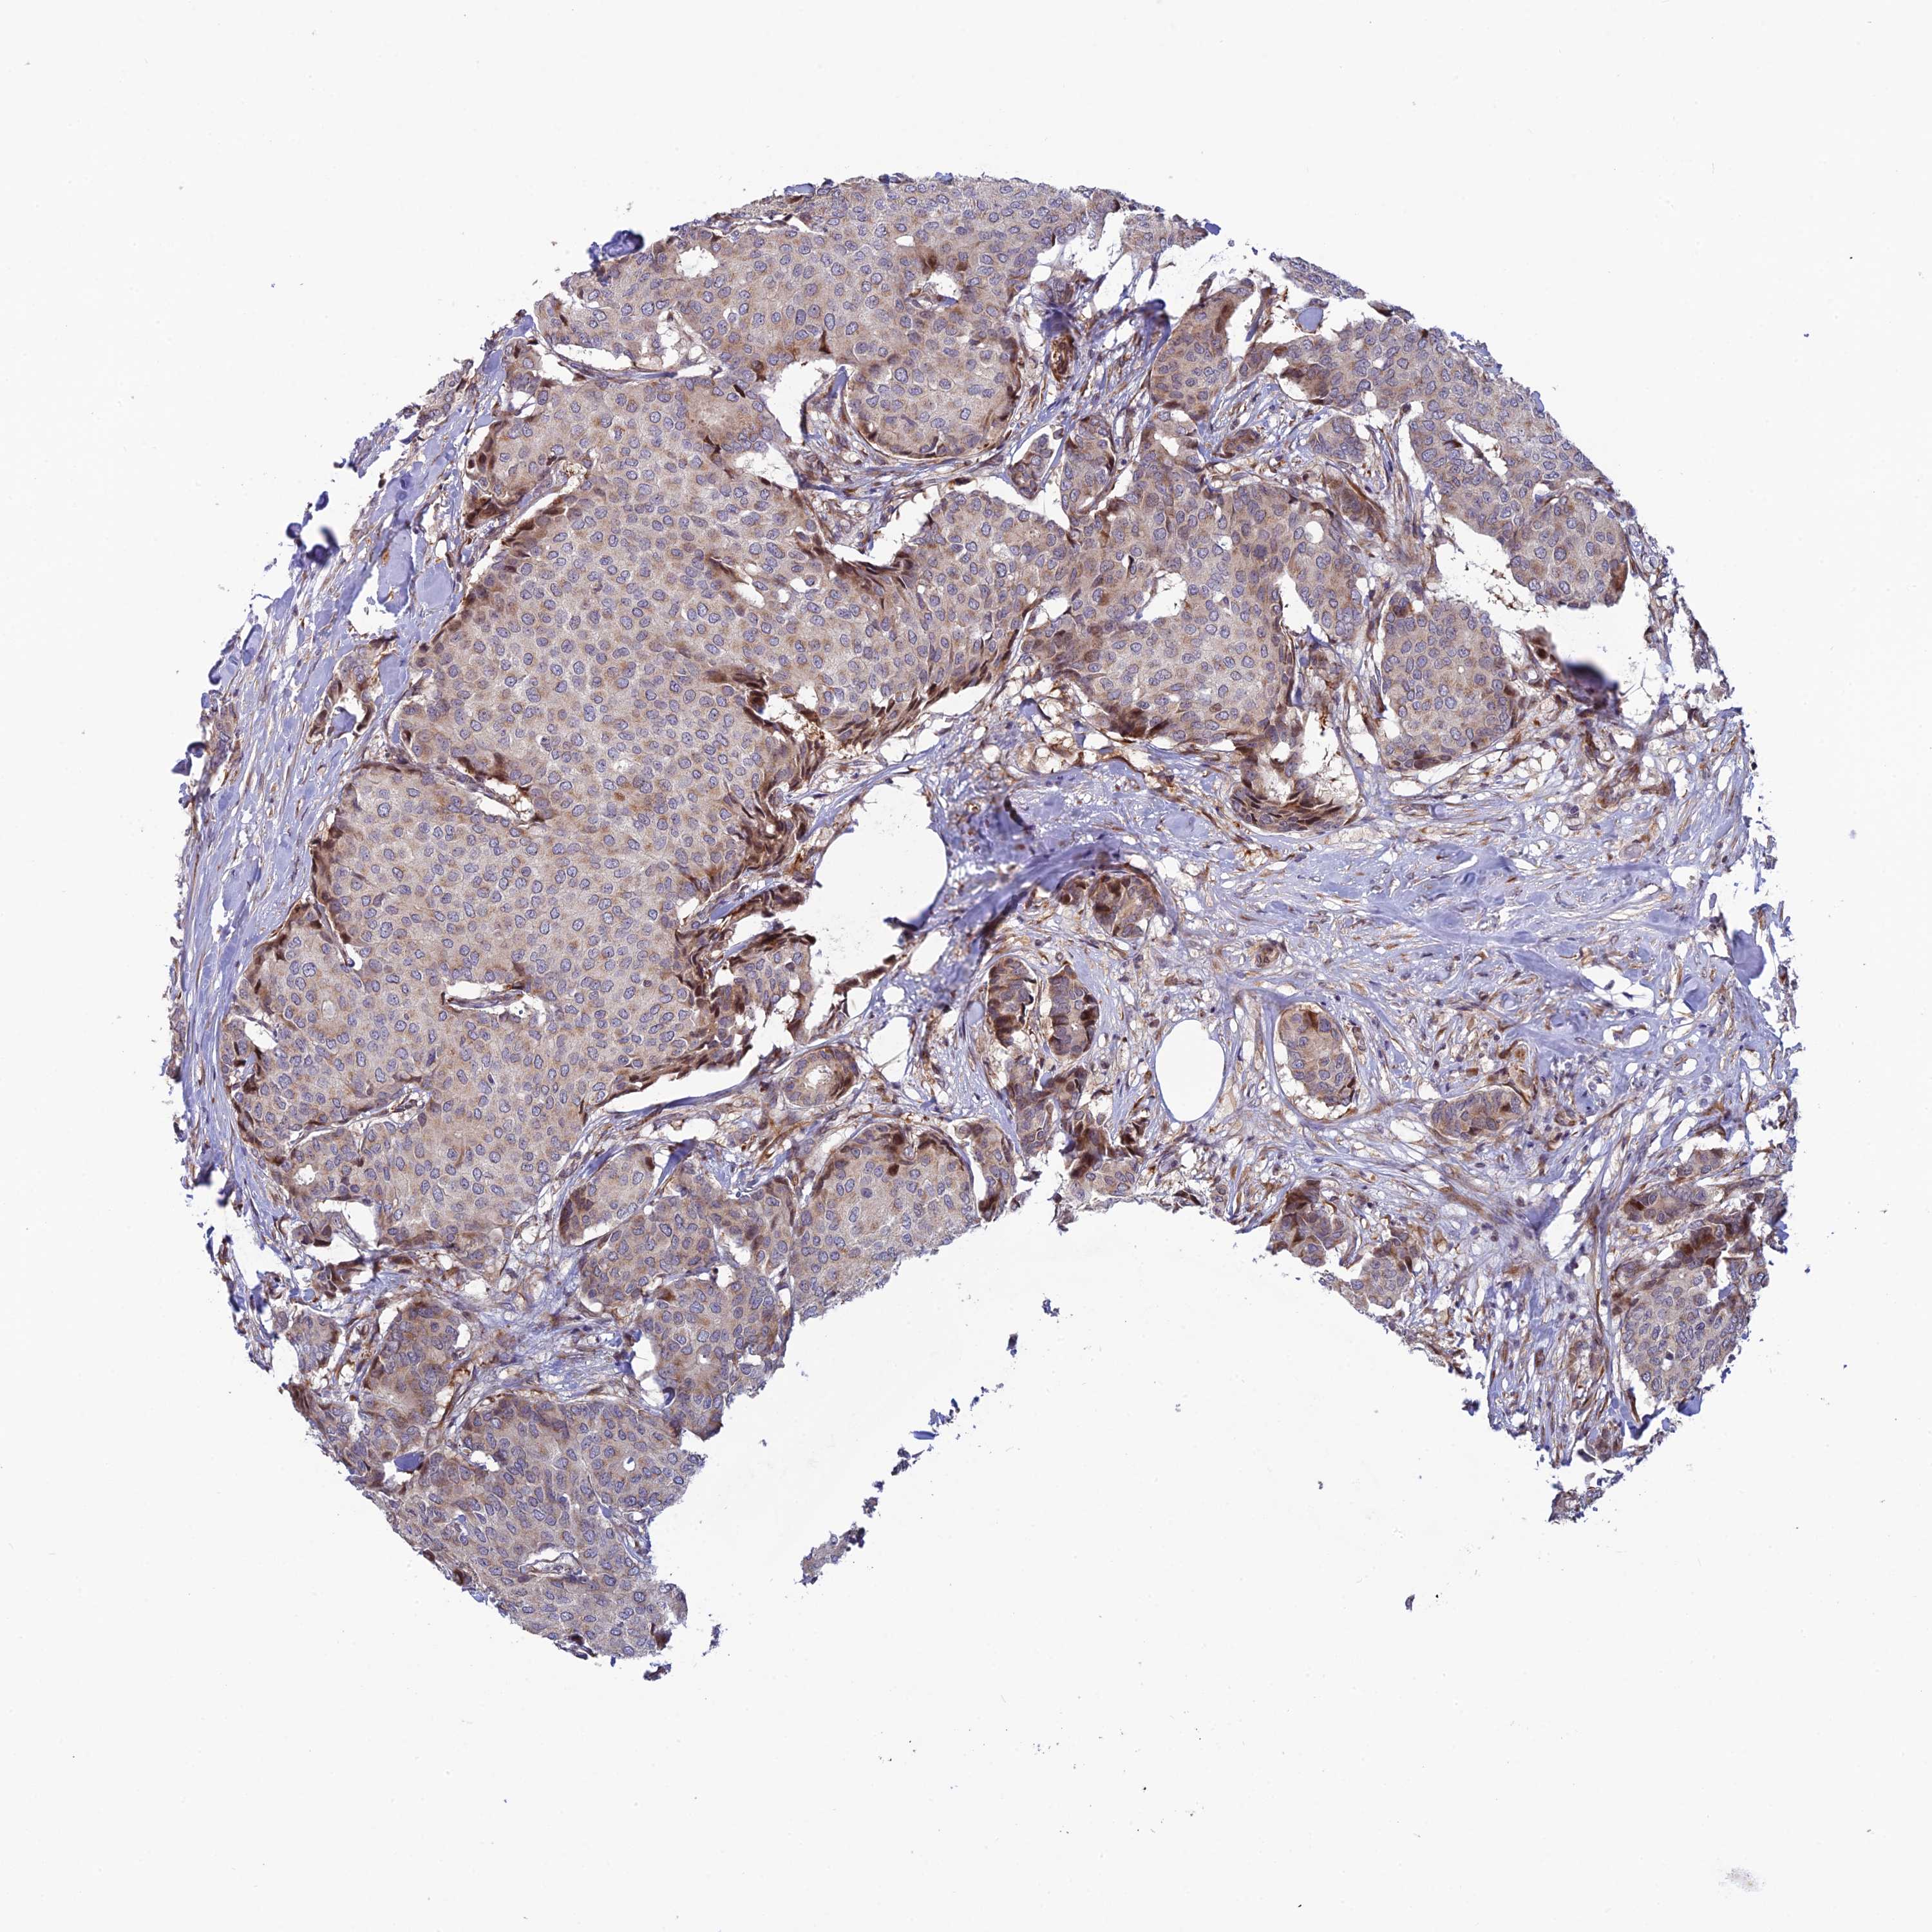

CANCER BREAST CANCER Show tissue menu

BRCA TCGA BRCA VALIDATION PROTEIN EXPRESSION